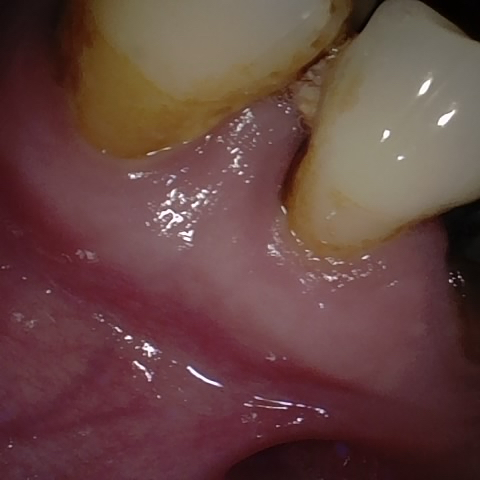

Annotated as "Good"